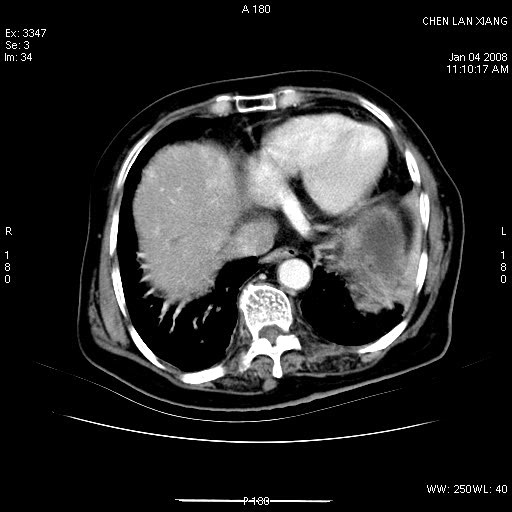

女,76岁,腹痛3-4天,b超示:肝内实性肿物,胆囊强回声,胆总管扩张.

1 胆总管末端结石伴肝内胆管结石,肝内外胆管扩张。2 胆囊扩大,胆囊壁不规则增厚,内见软组织密度影。考虑:慢性胆囊炎,不除外胆囊癌!

胆囊密度增高,增强后周边肝组织及胆囊窝下部周边软组织延时性不规则强化.然胆囊壁未见明显不规则增厚及肿块.左侧肝内胆管及胆总管下段结石伴胆系扩张.

考虑;胆囊炎(黄色肉芽肿性胆囊炎?),左侧肝内胆管及胆总管下段结石.

标题: 肝右叶病灶

胆囊癌侵犯肝右叶?

1)胆囊癌伴肝脏转移。2)胆总管下端结石、肝内胆管结石伴肝内外胆管扩张。